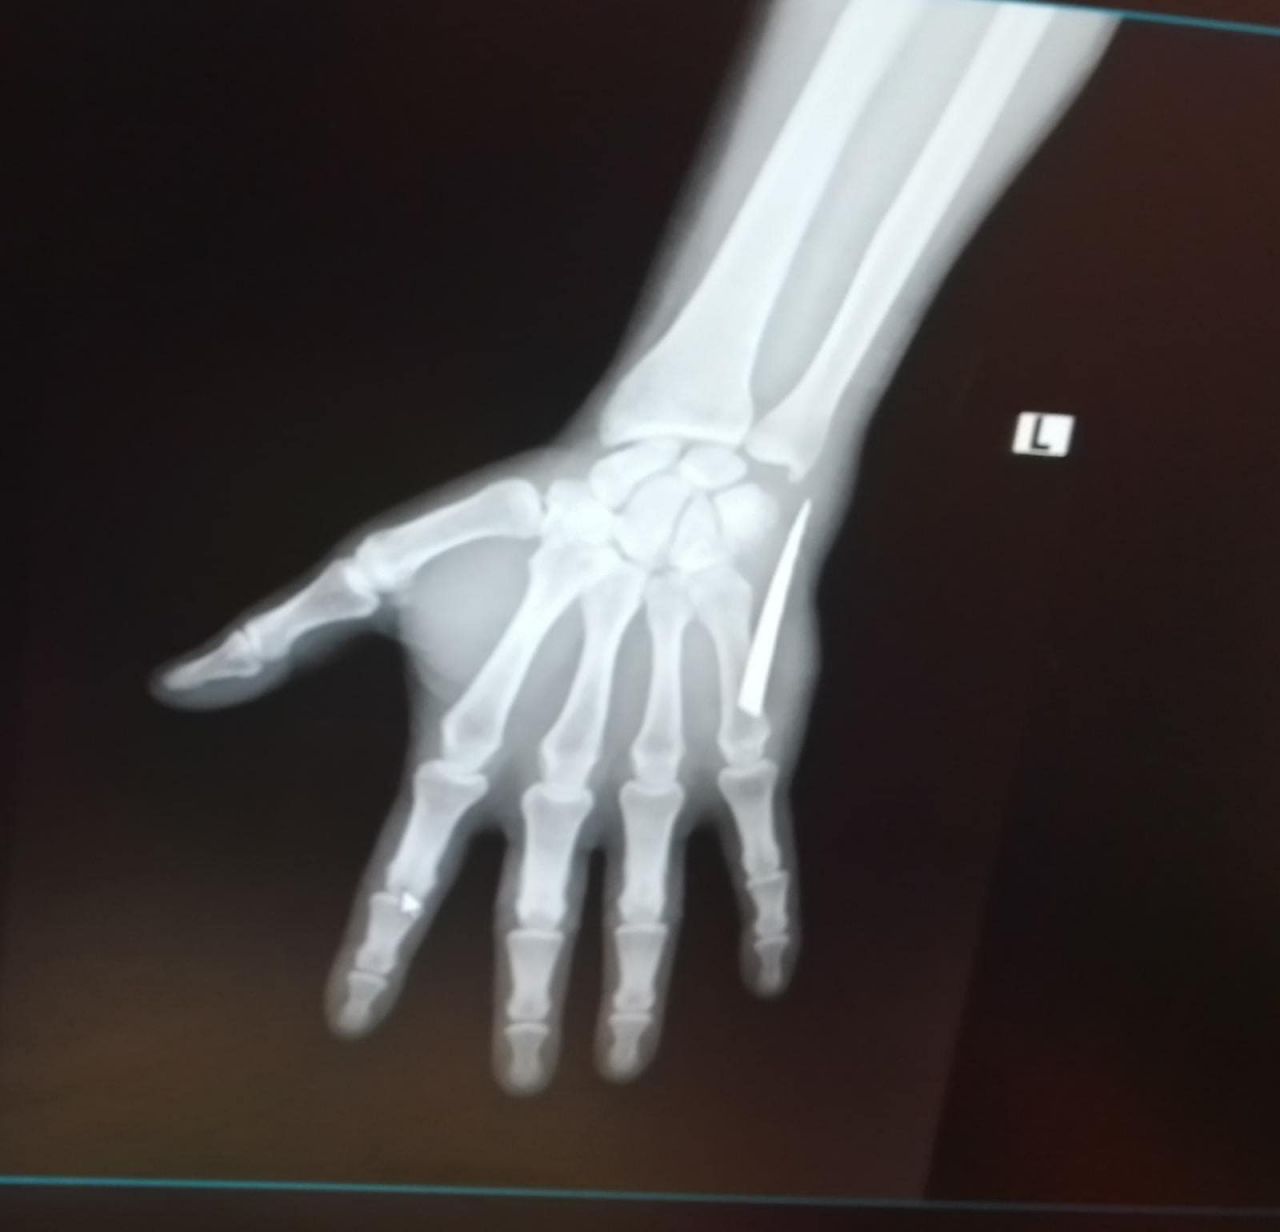

Sürekli kanama yapmaya başladı. Bu sebepten ötürü birkaç defa hastaneye gittiğimde pansuman yapıp gönderdiler. Film çekilmesini istedim, ‘Kırık, çıkık için film çekilir bu kadar yara için film çekilmez’ dediler. 28 Kasım Pazartesi günü daha şiddetli bir ağrıyla uyandım. Elime baktığımda bir parça olduğunu hissettim. Küçük bir parça sandım eşimle almaya çalıştık ama baya büyük olduğunu fark ettik. Bunun üzerine Çaycuma Devlet Hastanesi’ne geldik. Hemen röntgen çekildi ve elimdeki parçanın baya büyük olduğu söylenildi. Sonrasında ameliyat ile bıçağın parçasını aldılar.

“2 aydır elimdeki bıçak parçası yüzünden çalışamadım”5 santimetrelik bıçak parçasının yaşattığı acı nedeniyle elini kullanamadığını ve dolayısıyla da iki ay boyunca çalışamadığını söyleyen Köseli, Parmakta uyuşma, ağrı yapıyordu. Koluma engel olmaya başlamıştı. Güç kaybı da yaşayınca işsiz kaldım. Elimdeki bıçak parçası yüzünden hem elimden oluyordum hem de işsiz kaldım. Elim sürekli sargı içindeydi ve sürekli kanama yaşıyordum. Sargıyı çıkardığım zaman kanamam aşırı derecede artıyordu. Kan kaybı yüzünden kan oranlarımda da düşüklük çıktı. Kanama olmasına rağmen iyice temizlemeye çalıştım. O esnada elimin içinde bir şey olduğunu fark ettim. Elimle dışarıdan doğru ittirmeye başladım. Yüzeye doğru parça geldi. Korkutan gerçek, Çaycuma Devlet Hastanesi’ne gelince meydana çıktı. Çıkan parçada gördünüz gibi büyük ve tırtıklı bir bıçak. Tırtıklı bıçak normal bıçak yüzüne göre daha zararlı. Kolumda da baya hasar oluşturdu” dedi.